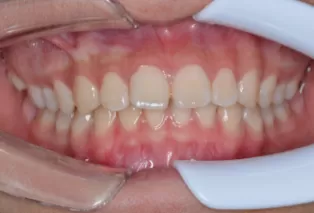

Photos intra-orales

teeth straightening aligners 4

teeth straightening aligners 5

teeth straightening aligners 6

teeth straightening aligners 7

teeth straightening aligners 8